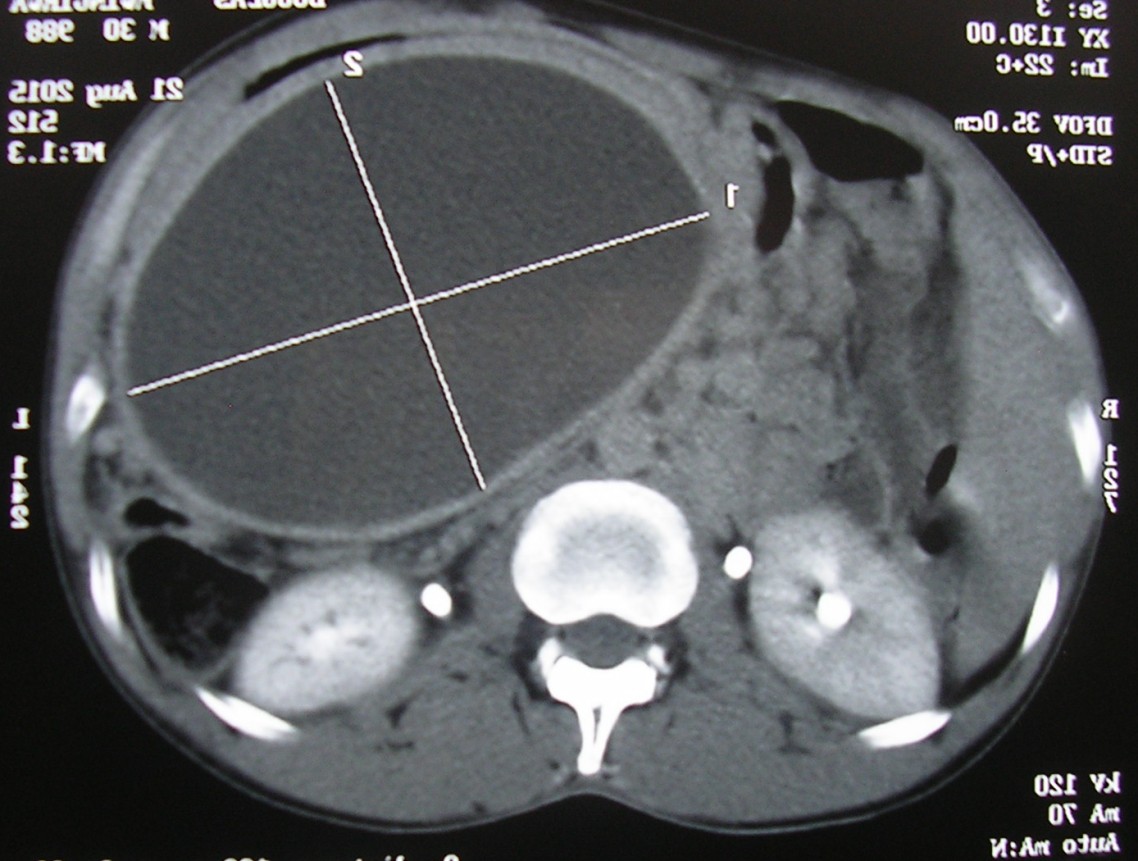

We immediately performed an abdominal ultrasound which allowed us to exclude any viscus perforation or peritonitis. On the other hand we have actually seen a round mass of the epigastrium, measuring about 12 cm in diameter. The mass was clearly a cyst, but the content was thick and rich in debris; it was clearly outside the liver parenchyma, and so it could not be an amoebic liver abscess.

Because of the epigastric location, immediately I have thought of a possible pancreatic pseudocyst, but I have decided to confirm the diagnosis with an abdominal CT scan. The latter imaging test was completely in accordance with the finding of the ultrasound, and I was a bit proud of that.